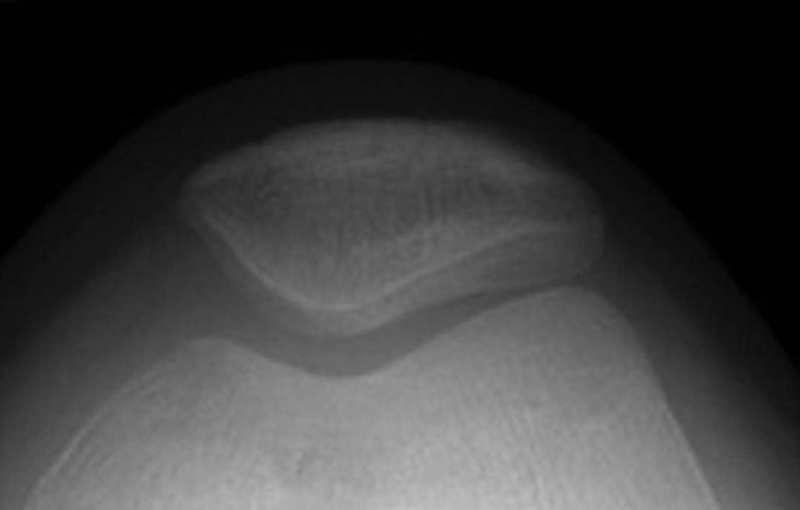

WibergⅠ型(图10):髌骨内外侧关节面均为凹面,且内外侧关节面宽度基本一致,髌骨嵴位于中央,约占10%。此型是比较理想的髌骨形态。

图10 WibergⅠ型髌骨轴位X线片